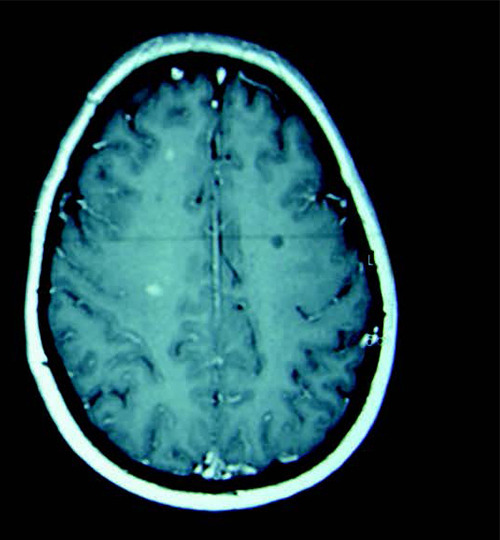

30 mai : Journée mondiale de la sclérose en plaques (SEP) ! Cette maladie neurologique auto-immune et dégénérative se déclare chez des patients âgés de 30 ans, en moyenne. Elle entraîne une destruction de la myéline, gaine protectrice des fibres nerveuses du cerveau et de la moelle épinière. Elle provoque, par paliers ou progressivement, des séquelles définitives, invalidantes, touchant la motricité, la sensibilité, la vision, le contrôle des sphincters. Ce sont 100 000 patients en France et 5 000 nouveaux cas chaque année. Les femmes sont 3 fois plus touchées que les hommes.

Image :  coll. C. Papeix.